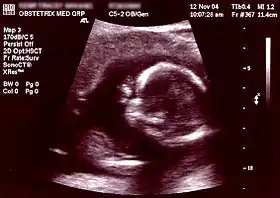

Ultrasound[8] Periodically Non-invasive/Invasive Abdominal or Transvaginal ~1 day - ~1 week Fetal development, neural tube defects, birth defects, and various other physical abnormalities (see below for specific ultrasound tests) NA

Ultrasonography is an example of a non-invasive diagnostic prenatal test.

Non-invasive Ultrasound detection Commonly dating scans (sometimes known as booking scans or dating ultrasounds) from 7 weeks to confirm pregnancy dates and look for multiple pregnancies. The specialised nuchal scan at 11–13 weeks may be used to identify higher risks of Downs syndrome. Later morphology scans, also called anatomy ultrasound, from 18 weeks may check for any abnormal development. Additional ultrasounds may be performed if there are any other problems with the pregnancy, or if the pregnancy is post-due. First or second trimester